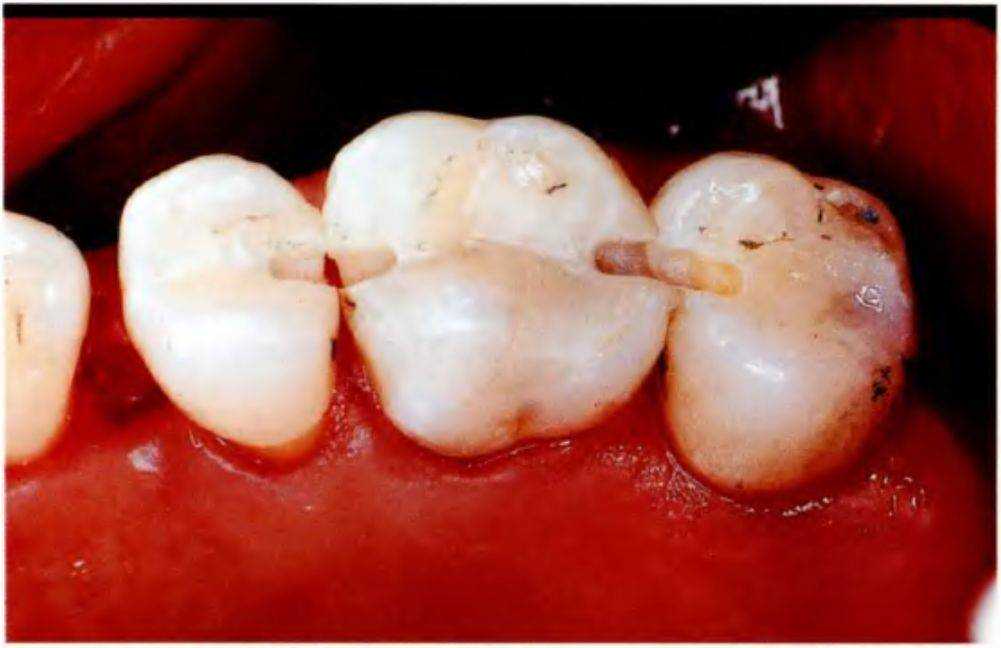

После нанесения первого слоя композита проводят промежуточную полимеризацию (рис. 4-2h). Подготовленное стекловолокно укладывают в борозду, при

необходимости его положение корректируют одноразовой щеточкой (рис. 4-2i). Второй слой композита наносят поверх волокна, полностью заполняя препарированную борозду (рис. 4-2 j). Композиту придают необходимую форму одноразовой щеточкой (рис. 4-2 к).